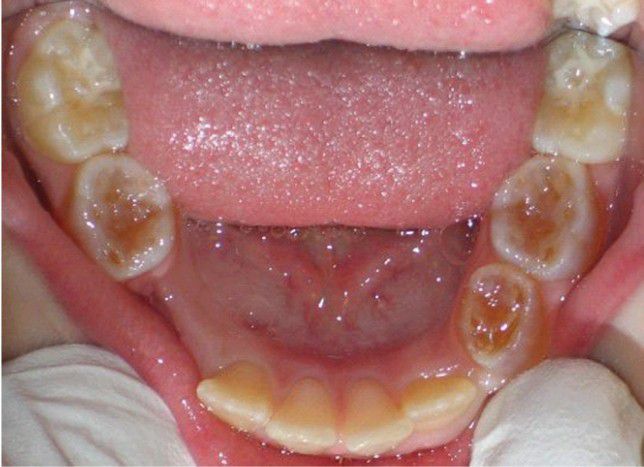

Dentin Dysplasia Type II (DD-II)

Dentition demonstrating darkened and translucent deciduous molars in association with permanent incisors and first molars that appear clinically normal.